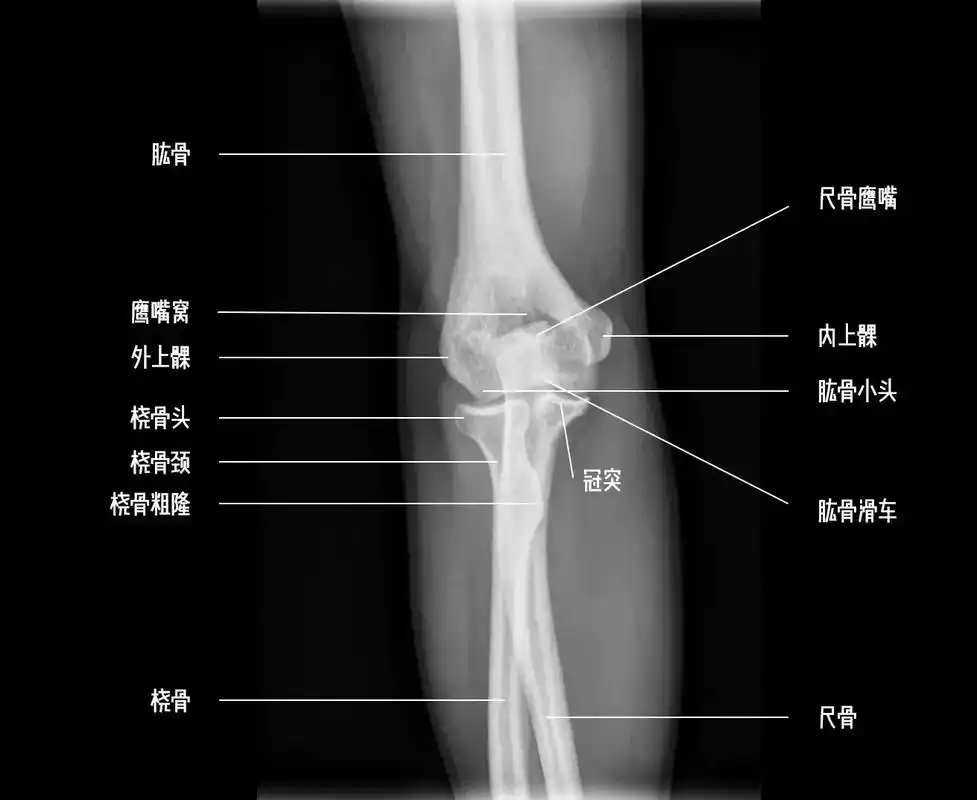

为了明白肘关节疼痛的原因,我们需要先了解一下肘关节的结构和功能.

肘关节

人类的肘关节

知识点肘关节